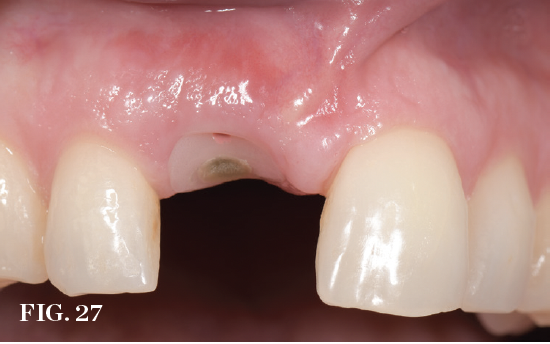

(27.) View of an immediate implant site 2-weeks postoperatively. Note the ideal design of the custom healing abutment supporting and guiding the marginal gingiva.

Figure 27

Immediate Tissue Guidance

In the immediate placement approach, implants should be planned and introduced using methods that create the possibility of placing a provisional restoration at the time of surgery to support the existing tissue contours. Although the restoration protocol is planned before treatment, the final decision of whether or not to follow through with it is based on the implant insertion torque/primary stability achieved as judged by the surgical clinician. Various techniques have been described that range from full-contour provisional crowns to partial guidance customized healing abutments with or without an overlying restoration. Delivering one of these transitional solutions can provide a barrier to retain any bone graft while potentially supporting the soft-tissue anatomy. In one 12-month randomized controlled trial, 3D ridge changes as expressed by soft-tissue resorption occurred following immediate placement; however, volume preservation was better when immediate provisionalization was carried out.36 Prosthetic guidance with custom healing abutments is recognized as an option to support the marginal tissue.37 Appropriate design is essential to have a positive impact on tissue anatomy support and outcomes (Figure 25 through Figure 27).